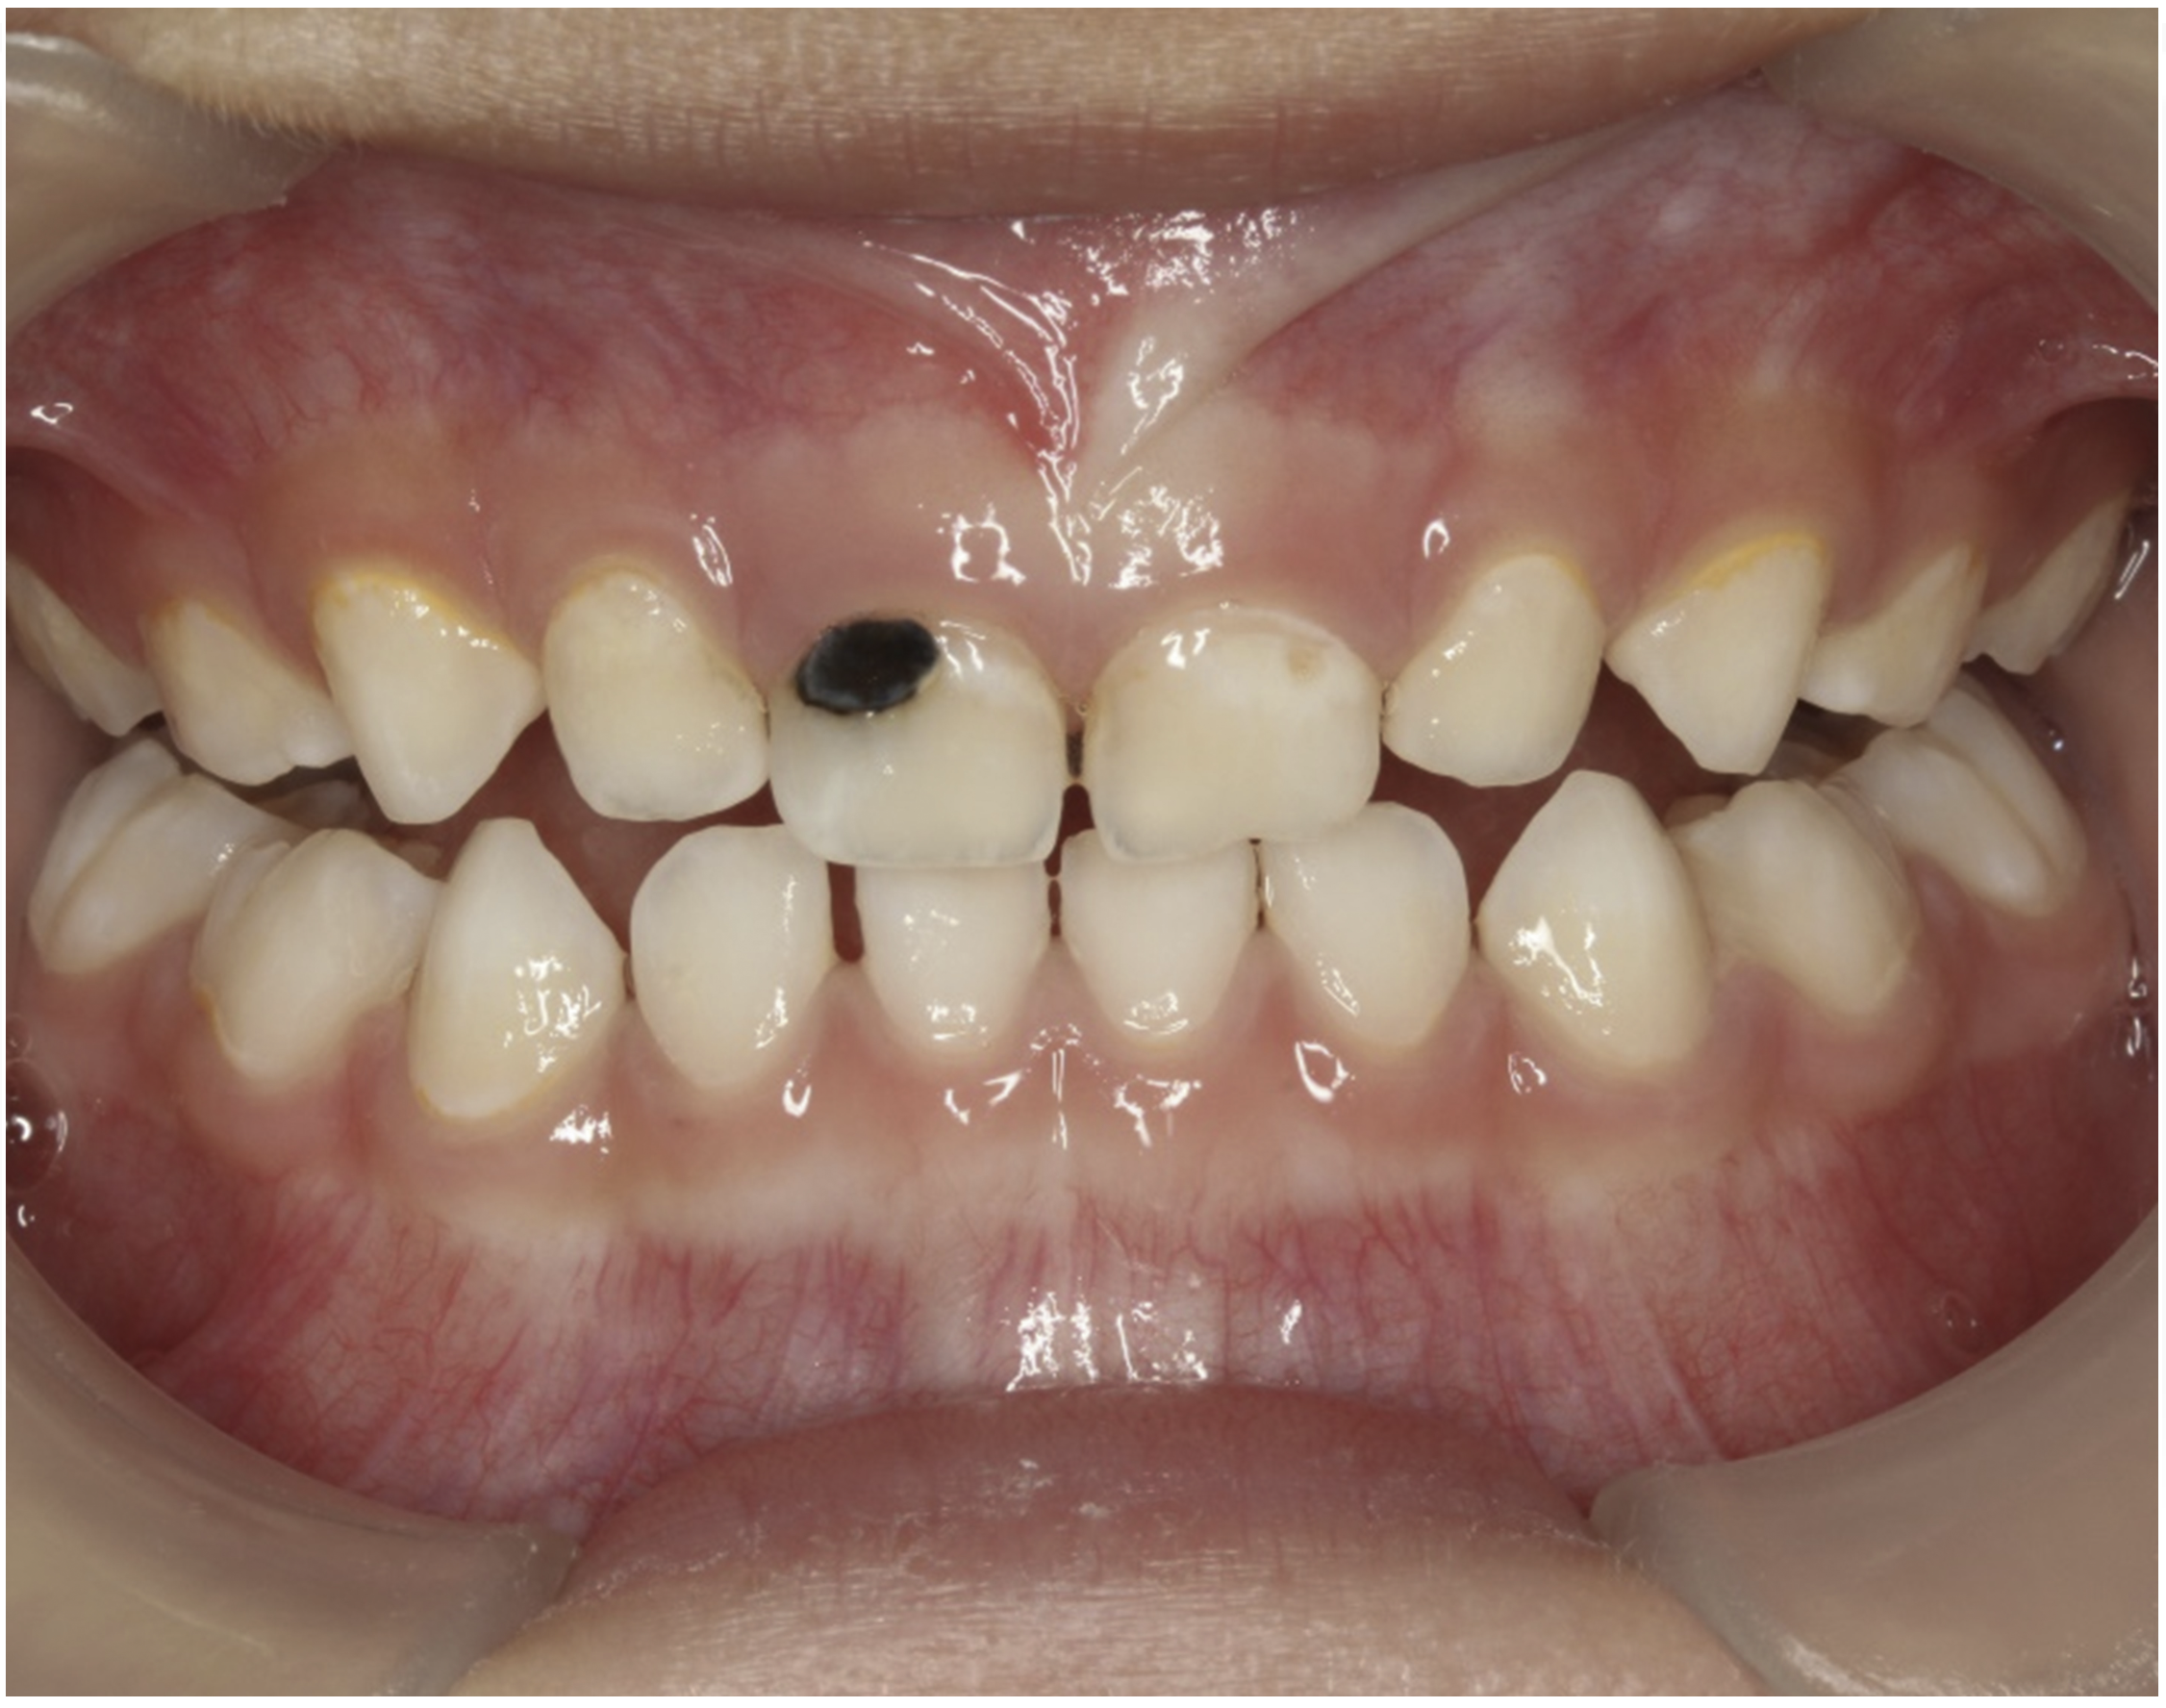

The inherent disadvantage of SDF is that the caries lesions will be stained black after SDF application. SDF stops caries progression by forming a hard, blackened, impermeable layer on the tooth surface that is resistant to caries (Figure 5 through Figure 9). The authors’ clinical observations are that the darker the color, the more likely the caries arrested. Some patients may not be pleased with the esthetics of this treatment outcome; therefore, it is important to inform the patients and parents (for child patients) about this treatment outcome. Moreover, SDF can stain clothes and the skin of the body. Though it does not cause any pain or damage, an SDF stain on skin cannot be easily washed away. It takes around 7 days for it to disappear, and the stain on clothes is permanent.22

There is no consensus on the frequency of application, and 38% SDF has been used annually or biannually on clinical trials in children23,31,33,34 and in elderly.30,35 Yee and his co-worker found one-off application of 12% SDF was ineffective in arresting caries in children.31 The present authors applied 38% SDF weekly for 3 weeks to speed up the process of caries arrest and for treatment of rampant caries.36 One of the present authors’ case reports demonstrated that three weekly applications of 38% SDF can arrest rampant caries and relieve pain from hypersensitivity on a teenager. The SDF-treated caries were found arrested, and they turned coal black in appearance (Figure 9).

Fig 8. Use of 38% SDF to arrest rampant caries in a young teenager: pre-treatment intraoral frontal view of rampant caries. (image from Chu, et al, 2014, ref 36 [reprinted with approval])

Figure 8

Fig 9. Use of 38% SDF to arrest rampant caries in a young teenager: frontal view of arrested caries after consecutive application of SDF for 3

weeks. (image from Chu, et al, 2014, ref 36 [reprinted with approval])